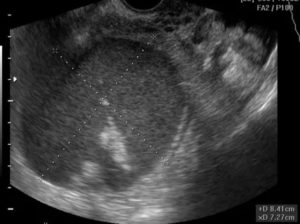

- УЗИ органов малого таза. Во время процедуры изучают матку и ее шейку, мочевой пузырь, придатки. Это позволяет обнаружить опухоли, определить их размеры и локализацию, выявить сопутствующие патологии.

- УЗИ с вагинальным датчиком, который позволяет произвести качественное обследование гинекологических органов.

Киста на ультразвуковом исследовании

Во время проведения обследования эндометриоидной кисты на аппарате УЗИ, она представляет двухслойную капсулу с содержимым и напоминает кисту желтого тела. Это служит поводом к повторному исследованию, так как киста желтого тела, в отличие от эндометриоидной кисты яичника, способна рассасываться самостоятельно, не прибегая к лечению и избегая операции.